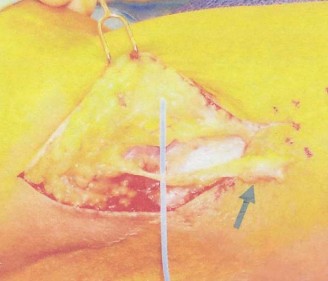

The correct answer is (C). When the native rotator cuff is irreparable, using a tendon transfer is the next step. Since the force vector of the pectoralis major muscle is similar to that of the subscapularis, this tendon can be used as an effective tendon transfer, restoring internal rotation and humeral head centering and compression. The surgery is performed by detaching the pectoralis major from its humeral insertion and moving the insertion to the lesser tuberosity. The tendon of

the pectoralis major can run anterior to the conjoined tendon or can be transposed posterior to the conjoined tendon but anterior to the musculocutaneous nerve. This latter method more closely replicates the force vector direction of the subscapularis, but has not been shown to lead to better outcomes (see Fig. 2–20). A latissimus dorsi tendon transfer is also sometimes used for irreparable subscapularis tendon tears.

Figure 2–20_Pectoralis major tendon transfer. Left: partial tendon transfer. Right: complete tendon transfer. Both use a subcoracoid approach. (From Omid R, Lee B. Tendon transfers for irreparable rotator cuff tears. _J Am Acad Orthop Surg. 2013;21(8):492–501.)

Subscapularis tendon repair is by definition impossible since this is an irreparable subscapularis tendon tear (Answer A). A tenotomy of the long head of the biceps (Answer B) would likely be performed as a part of the tendon transfer surgery, but would not by itself help in restoring function. A reverse total shoulder arthroplasty (Answer D) is used for massive, irreparable rotator cuff tears of the anterosuperior rotator cuff but not for subscapularis tears, as in this question. A supraspinatus tendon transfer (Answer E) is not a surgery that has been described for irreparable subscapularis tendon tears.